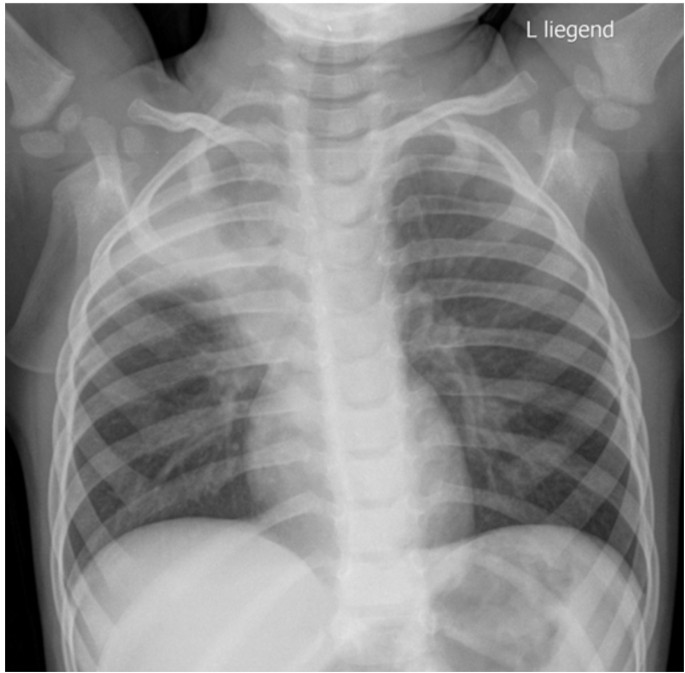

Тимомегалия: что это такое и как проявляется